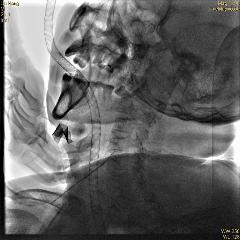

術中的X光線顯示,異物仍然在食管入口平面,只是它“不露面”,鏡子就無可奈何,沒法把它拽出來。

術中X光線顯示異物在食管入口平面

▲ 術中醫(yī)生嘗試用穿刺針套住

▲ 術中X線監(jiān)視下內鏡取出異物